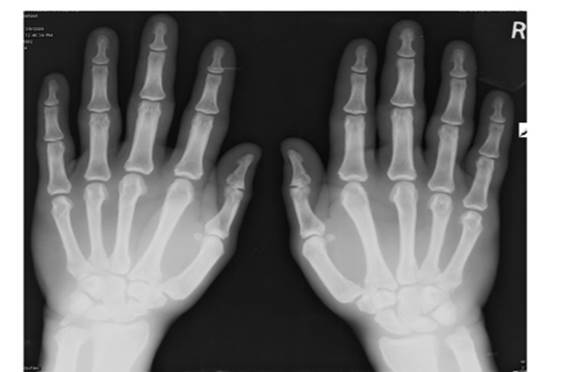

Объективті: науқ астың дене бітімі дұ рыс, тамақ тануы дұ рыс, есі анық, адекватты. Тері жабындылары – пальмарлы эритема, пальпацияланатын пурпура (фотоны қ ара).